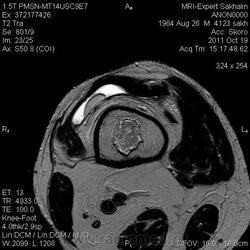

Инфаркт костного мозга на мрт

Мужчина с жалобами на боль в коленном суставе.Пришел сразу к нам по направлению врача с подозрением на ДОА, подагрический артрит.Рентгенограмм нет.

Я так понимаю, Вас смущают изменения в диафизах бедренной и большеберцовой костей?

инфаркт костного мозга